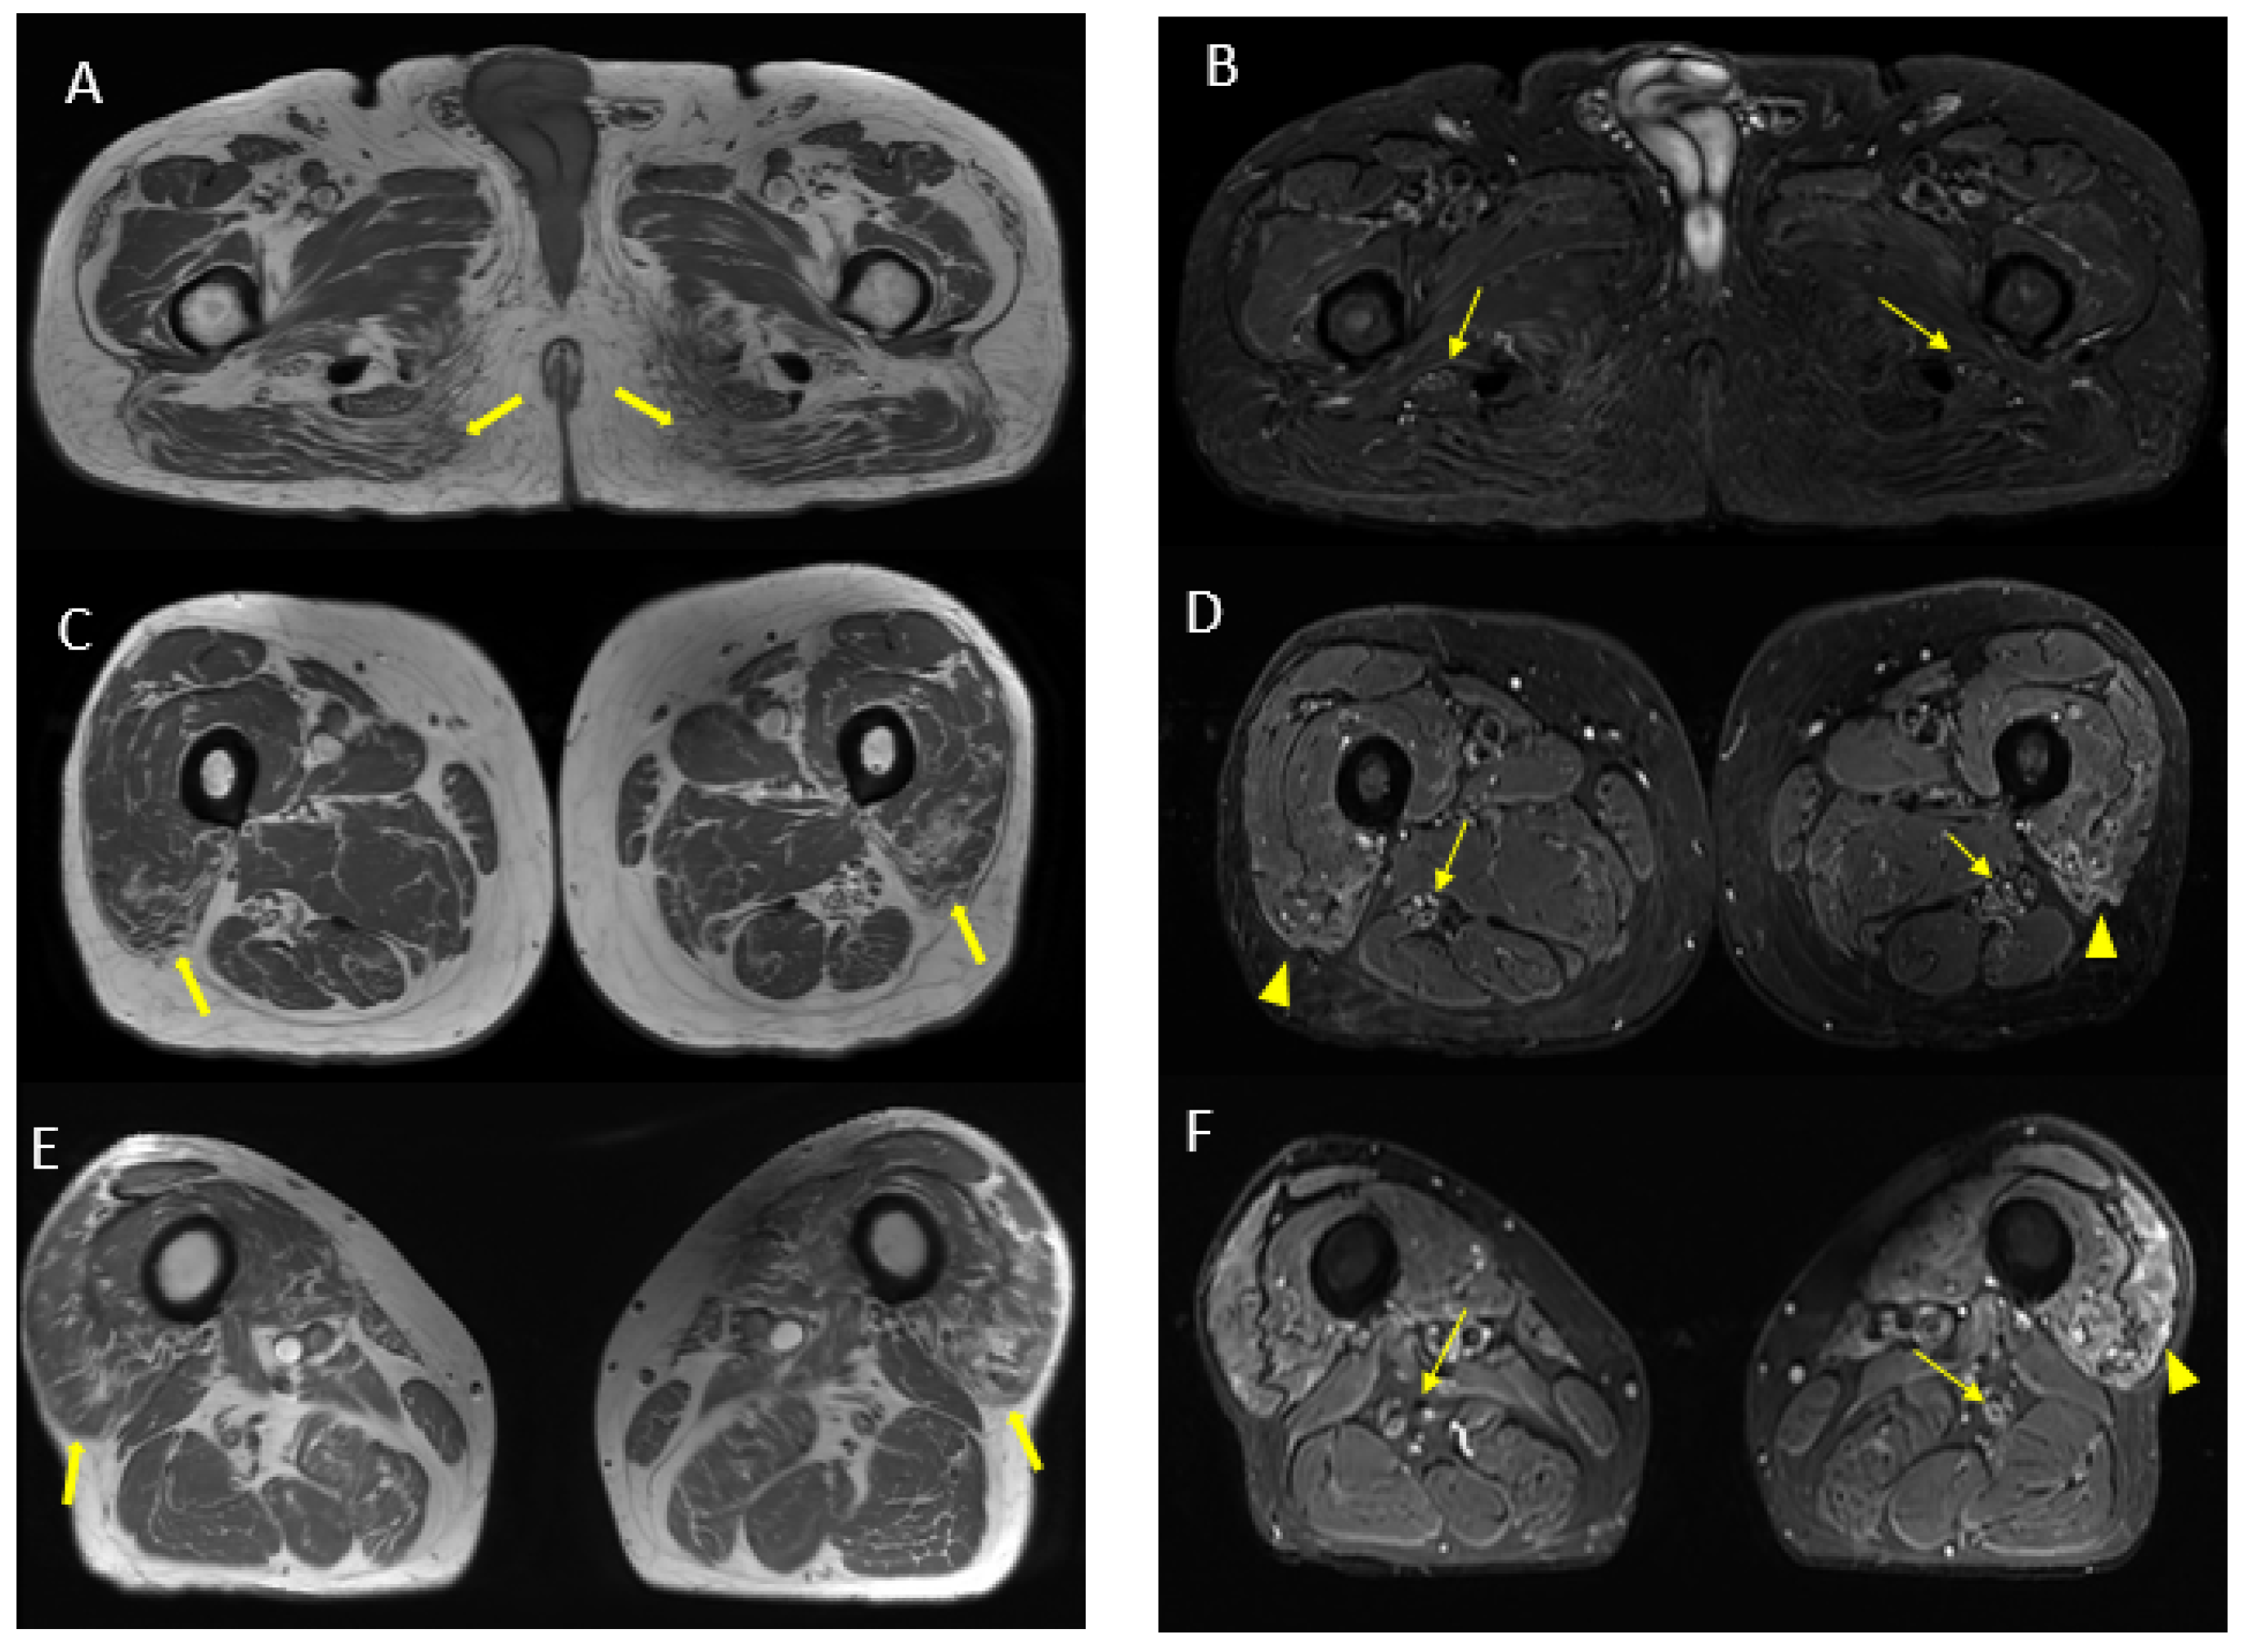

Figure 7.

Axial 2D MR of sciatic nerve; on the left are the T1w images and on the right are the T2 STIR images. Bilateral and symmetrical sciatic nerve T2 enlargement and fascicular hyperintensity at the level of the gluteal region (thin arrows (B); CSA of sciatic nerve of 103 mm2 on the right; 90.1 mm2 on the left) and at the mid-thigh (thin arrows in (D,F)). Mixed, acute and chronic denervation of the muscles of the anterolateral compartment of the thigh with denervation edema (hyperintensity in STIR, arrowheads in (D,F)) and fat replacement (thick arrows in (C,E)). Mainly chronic denervation of the gluteal muscles (hyperintensity in T1w, thick arrows in (A)).